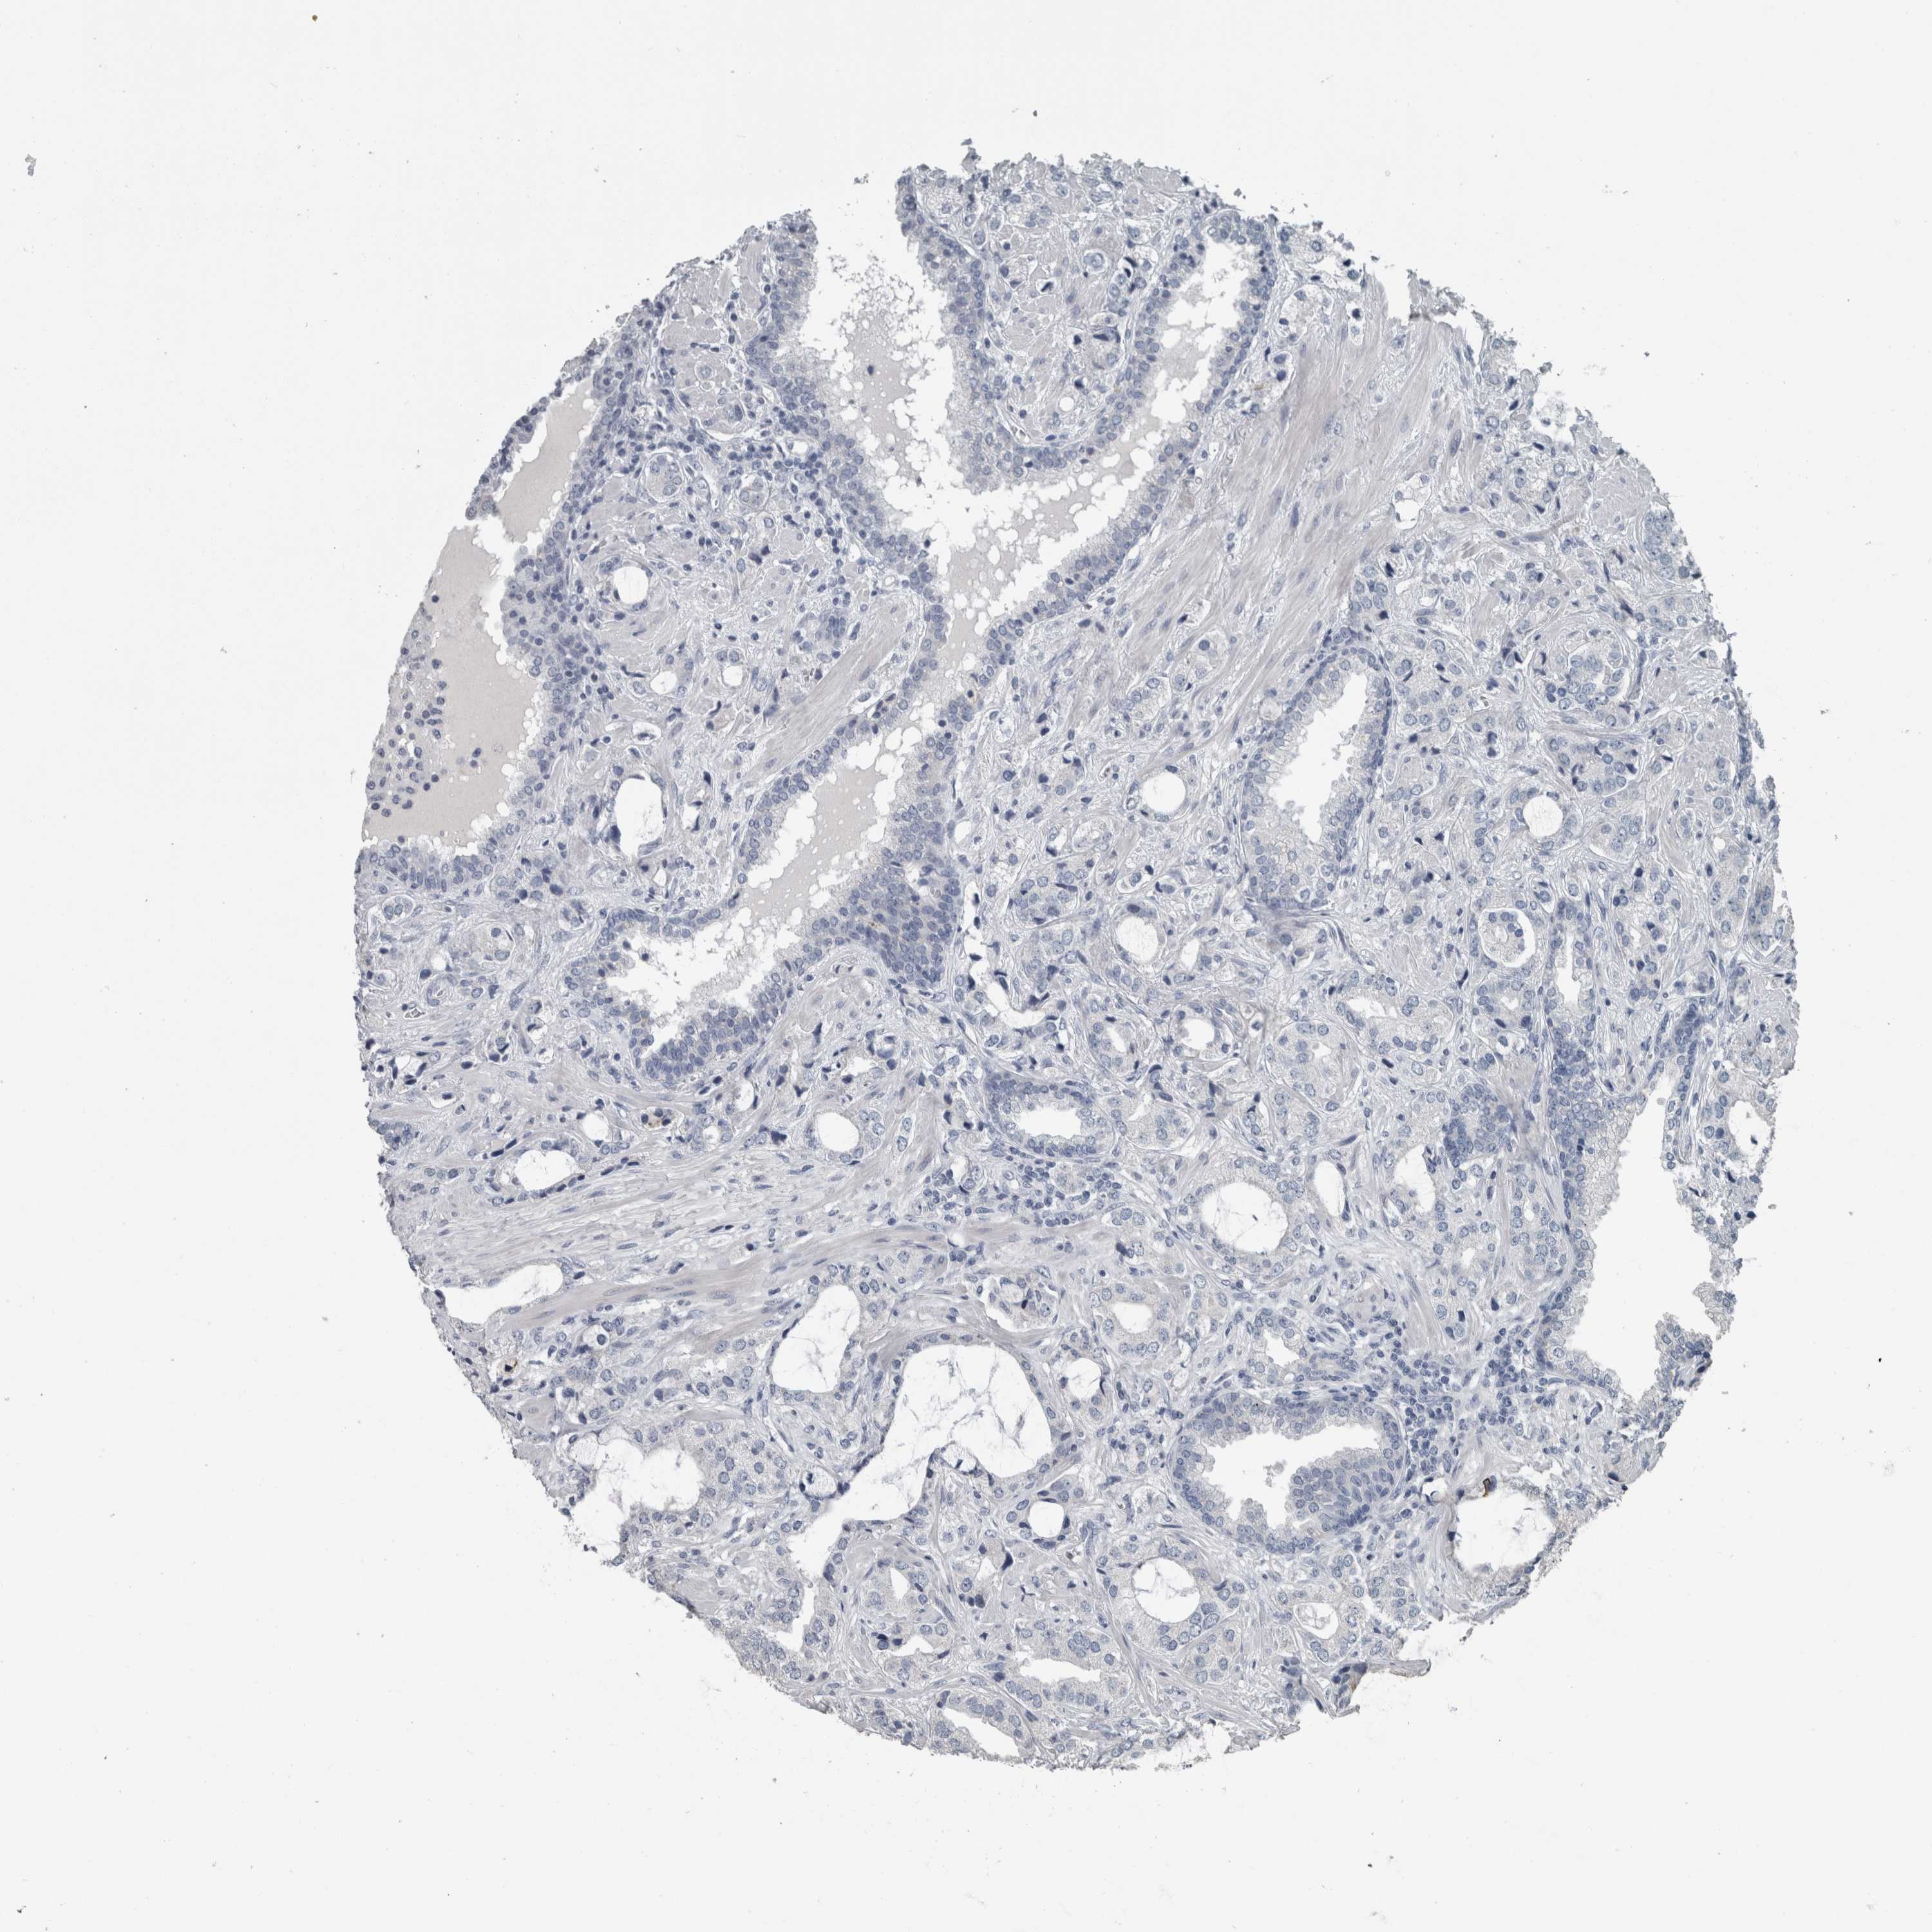

PROSTATE CANCER - Protein expressioni

A mouse-over function shows sample information and annotation data. Click on an image to view it in a full screen mode. Samples can be filtered based on level of antibody staining by selecting one or several of the following categories: high, medium, low and not detected. The assay and annotation is described here.

Note that samples used for immunohistochemistry by the Human Protein Atlas do not correspond to samples in the TCGA dataset.

Antibody stainingi

Antibody staining in the annotated cell types in the current human tissue is reported as not detected, low, medium, or high, based on conventional immunohistochemistry profiling in selected tissues. This score is based on the combination of the staining intensity and fraction of stained cells.

Each image is clickable and will lead to virtual microscopy that enables deeper exploration of all samples and also displays staining intensity scores, fraction scores and subcellular localization as well as patient and tissue information for each sample.

Antibody CAB000032

Staining

High

Medium

Low

Not detected

Intensity

Strong

Moderate

Weak

Negative

Quantity

>75%

75%-25%

<25%

None

Location

Nuclear

Cytoplasmic/membranous

Cytoplasmic/membranous,nuclear

Adenocarcinoma, High grade

Adenocarcinoma, Low grade

Adenocarcinoma, Medium grade